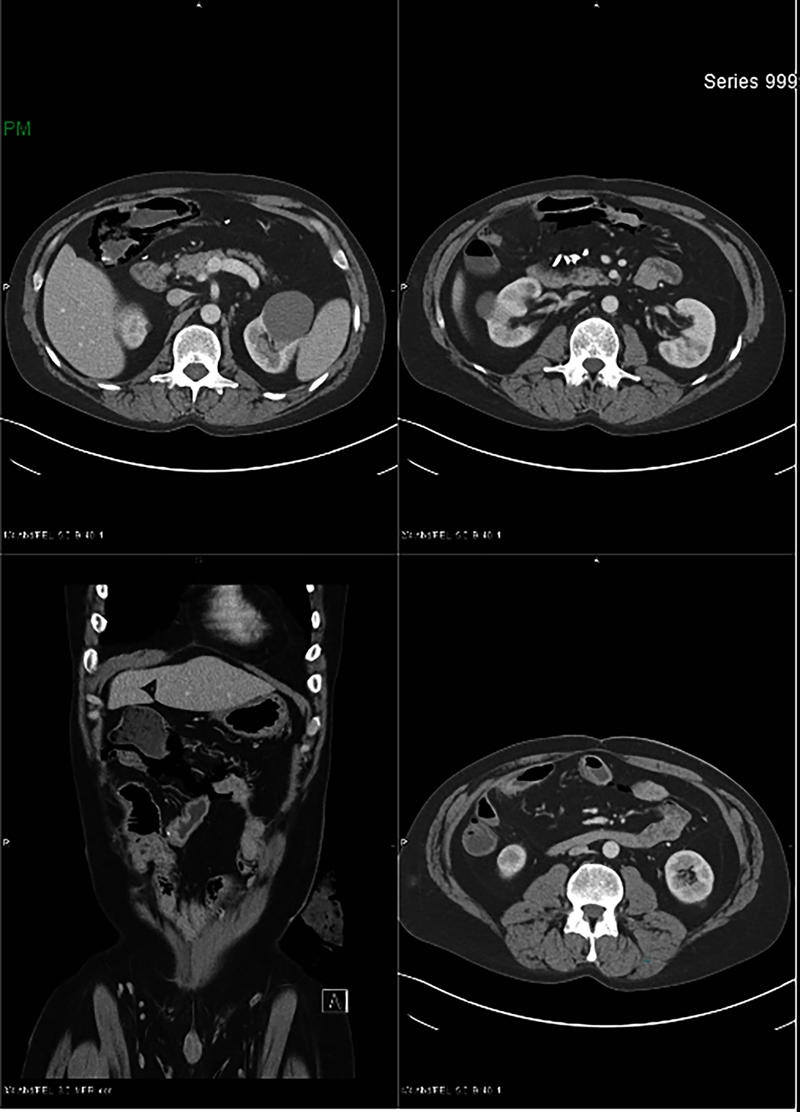

On admission, a CT scan (Figure 1) revealed extensive small bowel pneumatosis in the right upper quadrant without evidence of abscess, fistula, free air, free fluid, or portal venous gas. The patient was afebrile and slightly tachycardic, with a normal white blood cell count; additional laboratory results are shown in Table 1. Physical examination showed localized abdominal tenderness with positive rebound but no generalized peritonitis; the abdomen was soft, and the stoma was viable and productive.

Figure 1

Figure 1. Computed tomography with contrast reveals extensive bowel pneumatosis, especially in the right upper quadrant.